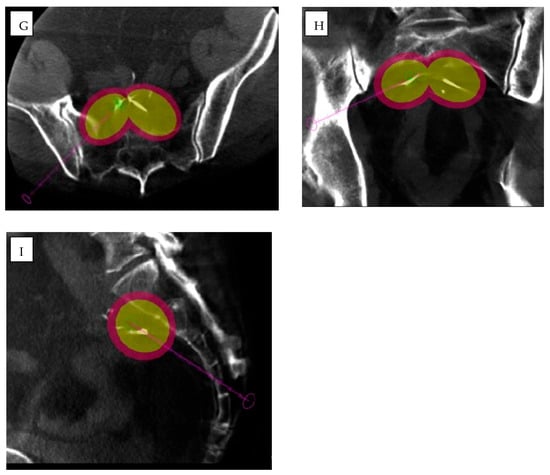

AI-driven image guidance systems such as XperGuide (Version 3.5.1, Philips Allura Xper FD20, Philips Healthcare), improve the precision of percutaneous procedures by delivering real-time three-dimensional needle guidance for percutaneous interventions [,] (Figure 3). XperCT software (Version 3.5.1, Philips Allura Xper FD20, Philips Healthcare) can be used to predict ablation volume [].

Figure 3.

A 61-year-old man with rectal adenocarcinoma previously treated with surgery, adjuvant chemotherapy, and radiotherapy. Pre-procedural MRI, including axial (A) and sagittal (B) T2-weighted images, (C) T1-weighted post-contrast image, and (D) diffusion-weighted imaging (DWI) with (E) apparent diffusion coefficient (ADC) map, together with (F) 18F-FDG PET/CT, demonstrate a heterogeneous mass in the presacral region consistent with local disease recurrence (red arrows). (G–I) Intra-procedural cone-beam CT (CBCT) in axial (G), coronal (H), and sagittal (I) planes obtained using XperGuide software (Philips Healthcare) for cryoablation probe placement (purple arrows), and XperCT (Philips Healthcare) for ablation zone prediction (purple and yellow circles).

XperGuide and XperCT are utilized in a wide variety of clinical settings, particularly in liver, lung, and renal tumor interventions. In liver tumors, particularly those located in the subphrenic region or near vital structures, their precise needle placement capabilities reduce the need for intraoperative patient repositioning and significantly lower the risk of complications such as infection and misplacement []. Similarly, in lung interventions, XperGuide enhances the accuracy of needle navigation in complex thoracic anatomies, thereby decreasing the number of passes required, reducing the risk of pneumothorax, and minimizing procedural trauma and subsequent interventions [,]. For renal tumors and spinal metastases, XperCT improves lesion visibility in areas where MRI may be limited, enabling more precise treatment planning and needle placement [,].

Both XperGuide and XperCT use intelligent algorithms for real-time trajectory optimization, motion compensation, and collision detection, but are not fully dependent on deep learning. These features enhance the safety of procedures by considering the patient movements—such as breathing—and avoiding important structures. Moreover, ongoing research seeks to integrate ML models that predict lesion response based on ablation geometry, suggesting optimal energy settings tailored to specific tissue characteristics. This would further personalize interventions, improving the likelihood of complete tumor ablation while minimizing damage to surrounding healthy tissues [,].